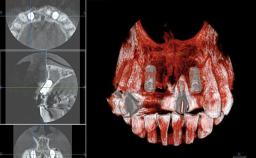

Replacement of Teeth 12 and 13 with Tissue-Level Implants

In 2001, a 48-year-old woman presented at a dental clinic with a failing fixed partial denture spanning from teeth 13 to 21. She was experiencing pain upon function, tenderness to palpation facial to tooth 13, and severe mobility of the prosthesis. Radiographic and clinical assessment revealed a subcrestal fracture of tooth 13, making its restoration unlikely. It was determined by the clinician that the tooth needed to be extracted prior to proceeding any further with dental care. After the extraction, the patient lost confidence in the progression of her treatment and sought consultation at the Center for Implant Dentistry. At her consultation visit in our clinic, an extra- and intraoral clinical examination revealed a medium lip line at full smile and an edentulous area spanning from 13 to 12 with both vertical and horizontal deficits in hard and soft tissue.

Bone Augmentation Horizontal|Staged|Vertical

Augmentation Materials Autogenous chips|Autogenous block(s)|Membrane

Bone Volume Deficient vertically or deficient vertically AND horizontally